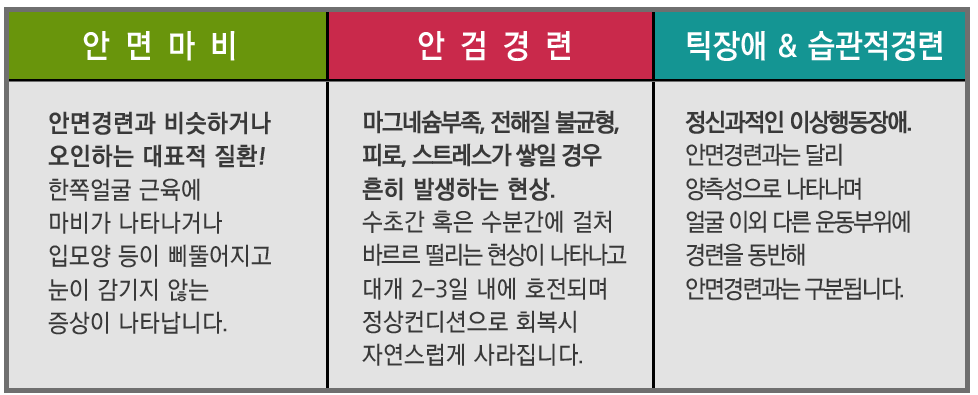

노인인구가 증가하면서 회복이 어려운 퇴행성 질환과 신경질환도 늘어나고 있다. 그중 우리가 외래에서 가끔 만나는 환자들은 파킨슨병을 앓고 있는 환자들이다. 파킨슨병은 걷기가 어려워지고, 팔이나 다리 근육의 떨림이 점점 심해지면서 일상생활에 많은 어려움을 겪는 질병으로 잘 알려져 있다. 따라서 손 떨림, 눈 떨림, 다리 떨림 등 경미한 떨림 증상이 나타나더라도 파킨슨병이 아닙니다. 고민을 안고 병원을 찾아오는 분들을 종종 만날 수 있습니다. 파킨슨병이란 무엇입니까?

파킨슨병은 주로 떨림, 근육 경직, 신체 움직임 둔화 등의 운동 이상을 일으키는 질환이다. 이 질환은 뇌의 신경전달물질인 도파민이 부족해 운동장애 증상이 악화되는 징후를 보인다. 주로 노년층에서 발생하며, 나이가 들수록 파킨슨병 발병 위험이 높아지는 것으로 알려져 있습니다. 파킨슨병은 회복이 쉽지 않지만, 조기에 진단하고 도파민 결핍을 해소할 수 있는 약물로 적절한 치료를 받는다면 큰 문제 없이 생활할 수 있으며 질병의 진행도 완화될 수 있다. 파킨슨병에는 어떤 약물을 주의해야 합니까?